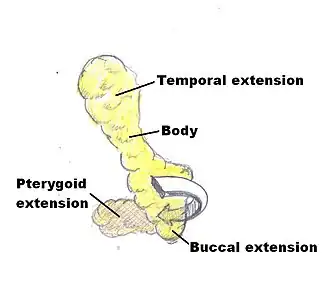

The buccal fat pad is composed of several parts, although exactly how many parts seems to be a point of disagreement and no single consistent nomenclature of these parts has been observed. It was described as being divided into three lobes, the anterior, intermediate, and posterior, “according to the structure of the lobar envelopes, the formation of ligaments, and the source of the nutritional vessels”.[1] Also, there are four extensions from the body of the buccal fat pad: the sublevator, the melolabial, the buccal, and the pterygoid. The nomenclature of these extensions derives from their location and proximal muscles.[4]

The anterior lobe of the buccal fat surrounds the parotid duct, which conveys saliva from the parotid gland to the mouth. It is a triangular mass with one vertex at the buccinators, one at the levator labii superioris alaeque nasi, and one at the orbicularis oris. The intermediate lobe lies between the anterior and posterior lobes over the maxilla.[1][4] The intermediate lobe seems to lose a significant amount of volume between childhood and adulthood. The posterior lobe of the buccal fat pad runs from the infraorbital fissure and temporal muscle to the upper rim of the mandible and back to the mandibular ramus.